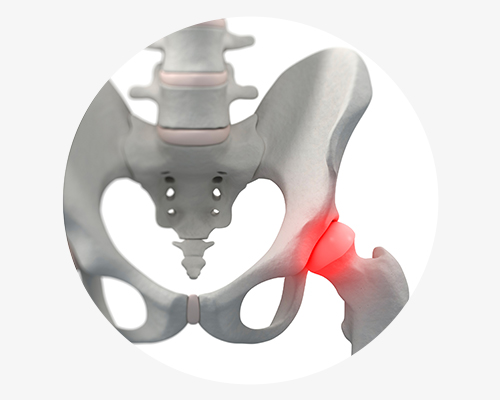

고관절충돌증후군

접히거나 안쪽으로 움직이는 회전운동을 할 때 대퇴골의 경부와 비구 사이

충돌이 일어나는것

으로 대퇴비구 충돌 증후군이라고도 합니다.